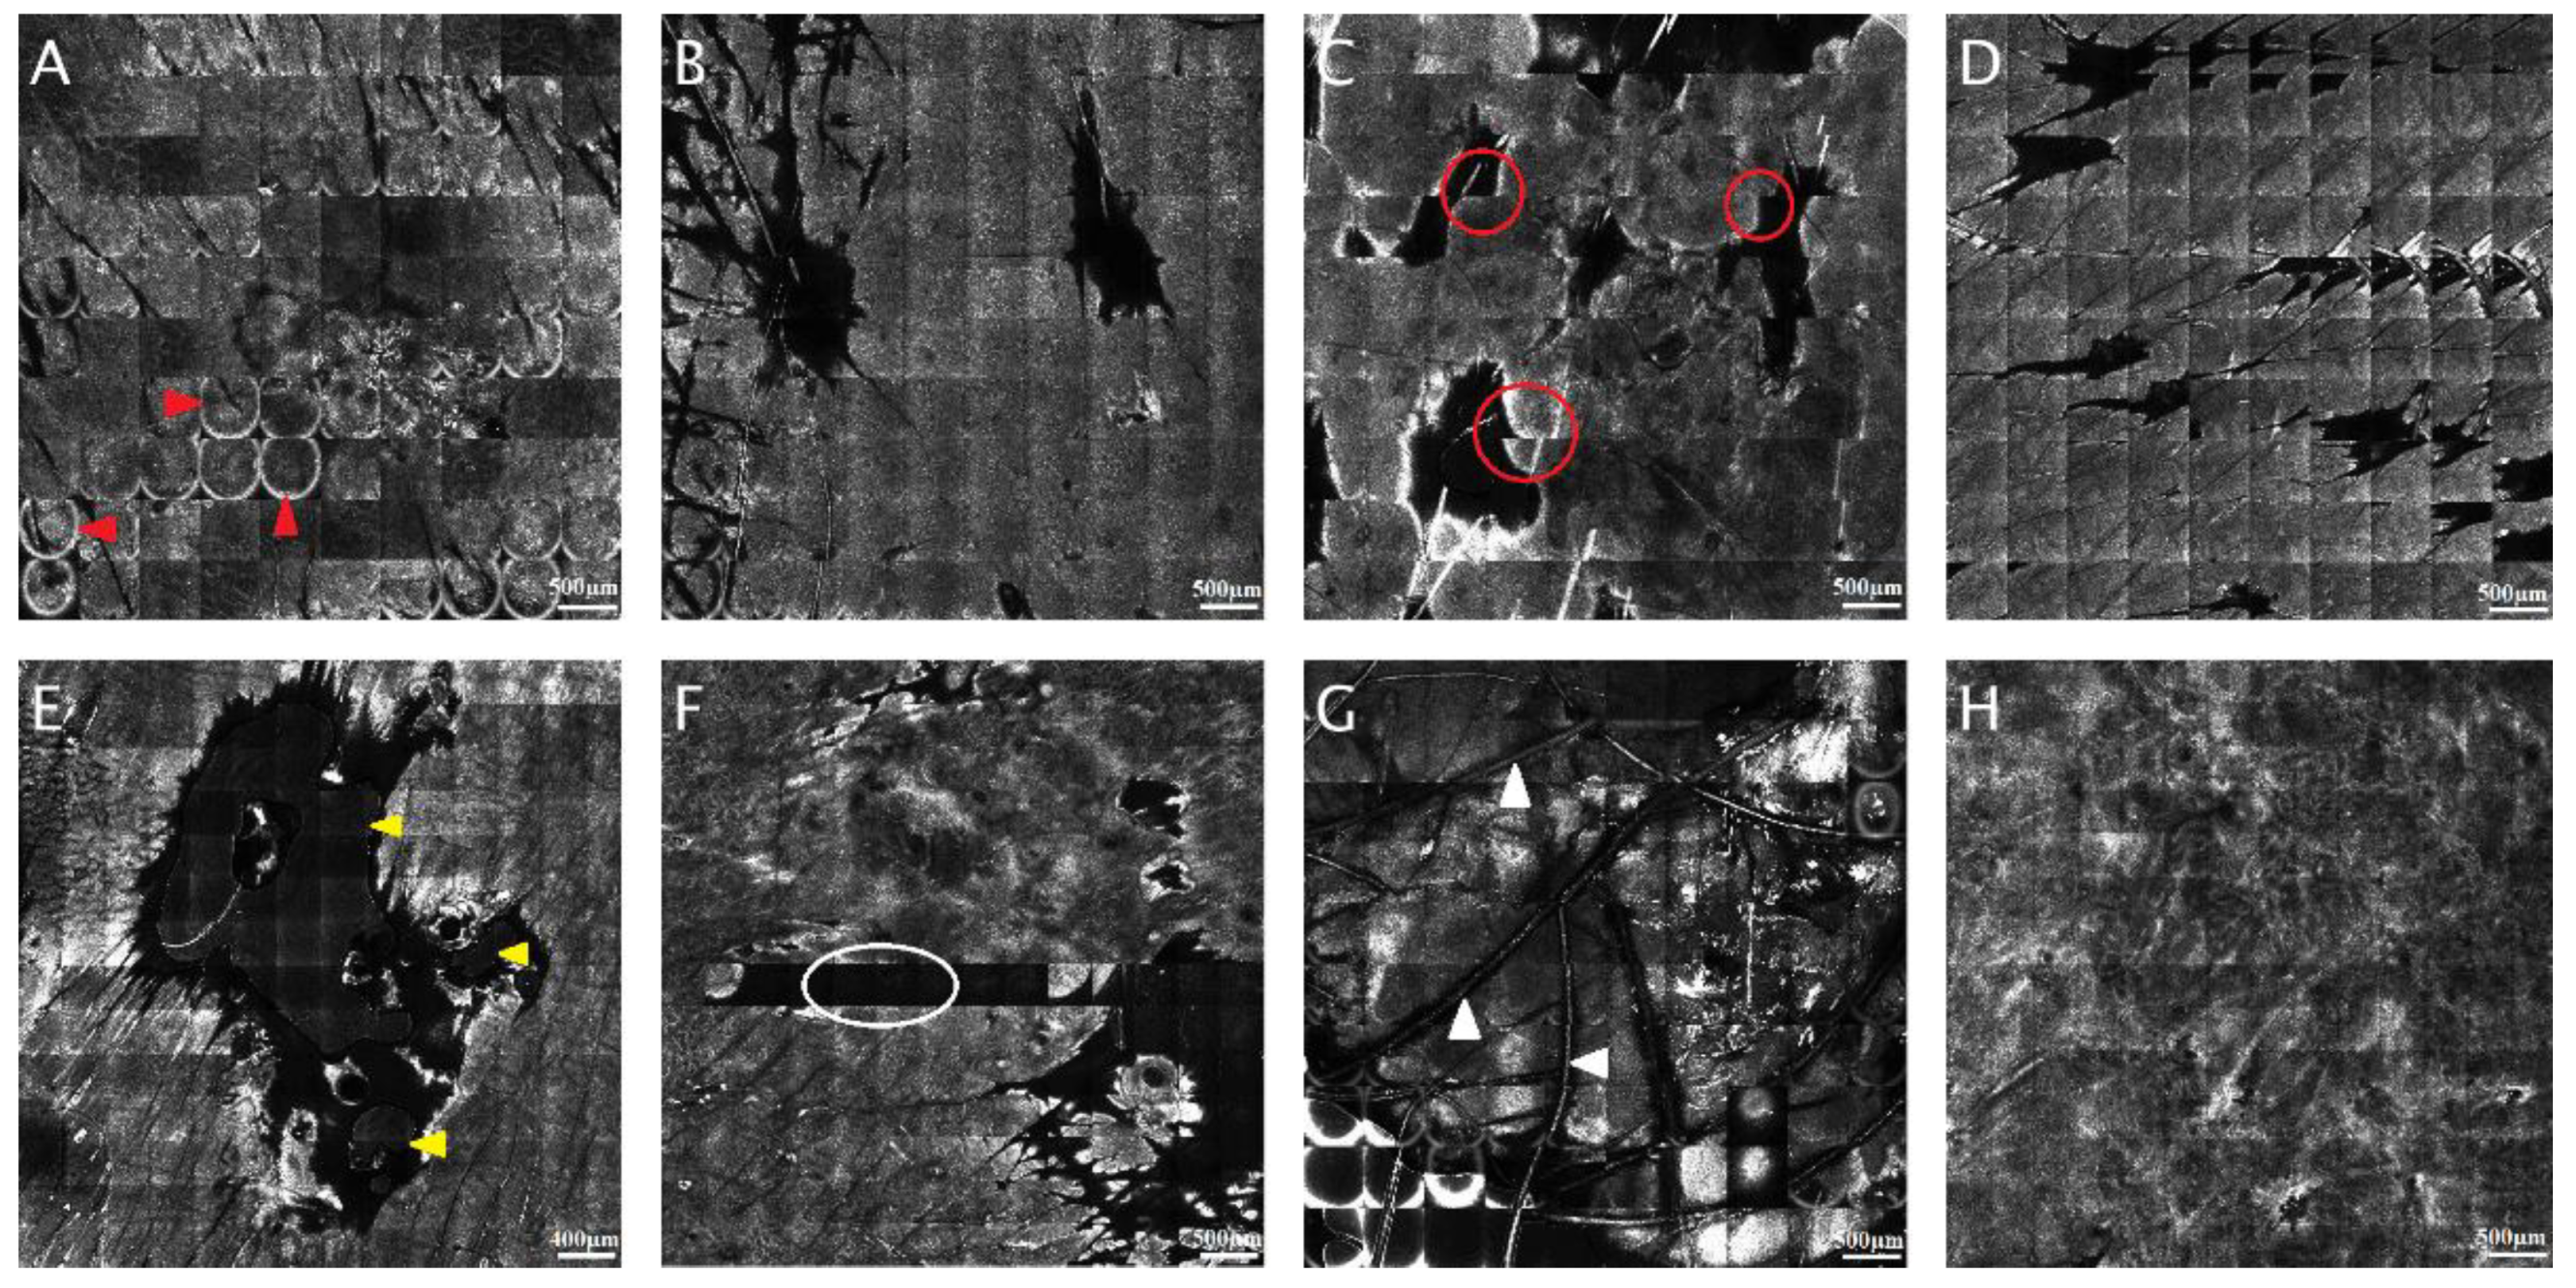

The most frequent artifacts seen in RCM images are relics related to reflection on the surface. That can appear in RCM mosaics due to the presence of corneal layer reflection in the form of hyper-reactive rings, or it can occur as a lighter contour of every single RCM mosaic compared with the rest of the image. Another type of artifact that shows the shifting and misalignment of sole RCM mosaics can be induced by the person’s movement, respiratory movements, talking, or even the heart beating. In the case of papules or nodules, bright or dark relicts appear in the region where the microscope and the skin are not touching [25]. In addition, in some RCM mosaics, air and oil bubbles can be seen commonly stuck by skin creases, hair follicles, or surface unevenness throughout the investigation. Occasionally, several individual images of RCM mosaics are underexposed or completely clear. Sometimes can appear changes in contrast due to the microscope’s automatic intensity control and several curved lines traversing the image, representing hair fibers. These artifacts are widespread, but, as long as they do not affect the entire mosaic rendering it unreadable, the images can still be helpful. Figure 1 shows the most common artifacts that appear in RCM mosaics.

Figure 1.

The most common reflectance confocal microscopy (RCM) mosaic artifacts. (A) Circular hyper-reflective rings caused by corneal layer reflection (red arrowheads). (B) Bright contour of each RCM picture (5 × 5 mm). (C) Sliding of single RCM images (5 × 5 mm); notice how there is no proper alignment of the images on different rows (red circles). (D) Repeating images in the RCM mosaic (5 × 5 mm). (E) Air and oil bubbles (yellow arrowheads). (F) Black individual images (white circle) without useful information in the RCM mosaic (5 × 5 mm). (G) Hair and bright relics (white arrowheads). (H) Correctly captured RCM mosaic. (RCM images courtesy of M.L.).